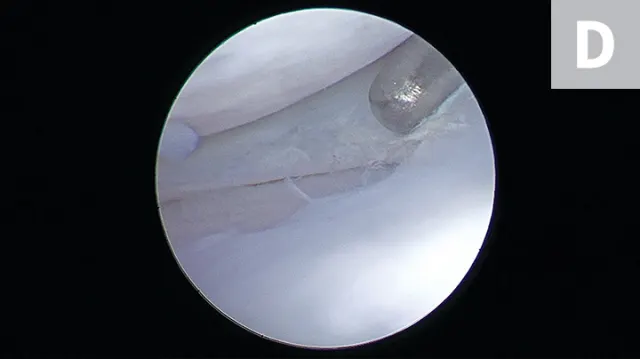

FIGURE 4A

Arthroscopic images showing a small bucket handle tear in the caudal pole of the medial meniscus (A; arrowheads). The meniscus is palpated with a meniscal probe (B; P). The torn portion of meniscus is removed with an arthroscopic shaver (C; S). After removal of the diseased meniscus, the remaining outer rim of the meniscus is left intact (D).